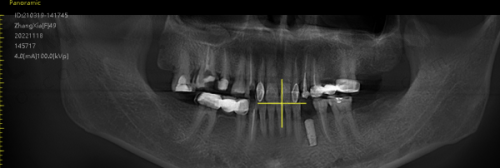

全方面检查:在进行种植牙手术前,患者需要进行全方面的口腔检查和身体检查。包括口腔X光片、CT 扫描等,以确定牙槽骨的情况和身体是否适合种植牙手术。如果有高血压、糖尿病等全身性疾病,需要先将病情控制稳定后再进行手术。